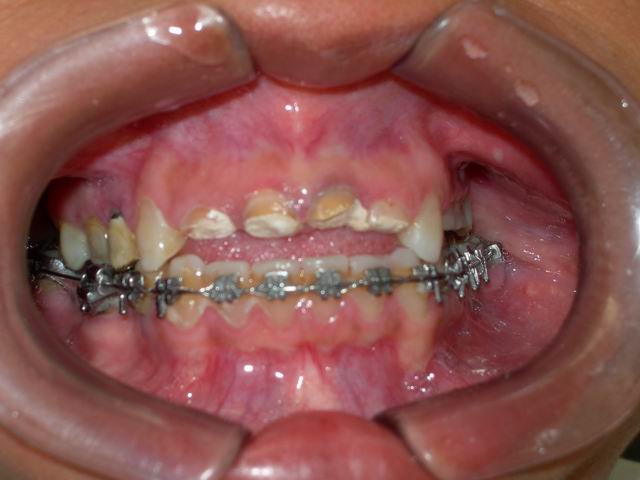

Tratamento ortodôntico prévio (vista frontal)

Caso concluído com próteses metalocerâmicas cimentadas